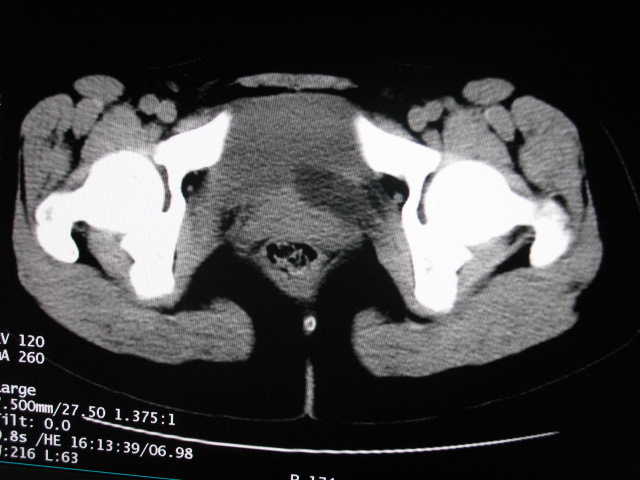

女,28岁,自觉腹部包块一年余

左侧为扩张的输尿管,一直延续到膀胱,那么它的上端应该是扩张的肾盂,但是在他的下方我们看到一个比较正常的肾,所以考虑左侧重复肾盂输尿管畸形。

考虑左侧双肾盂双输尿管畸形,其中一输尿管末端梗阻(不排除异位开口可能)并相应之肾盂及输尿管明显扩张积水。

考虑左侧双肾盂双输尿管畸形,其中一输尿管末端梗阻并输尿管肠管样扩张盂曲、肾盂囊状扩张积水。

左侧重复肾、双输尿管畸形。重复肾一般上位肾发育不良,易合并积水。

考虑左侧双肾盂双输尿管畸形,其中一输尿管末端梗阻(不排除异位开口可能,不知病人有无不自觉溢尿,有可能开口于阴道或宫颈,也可下端为盲端)并相应之肾盂及输尿管明显扩张积水。

术后证实是左侧双肾盂双输尿管畸形,巨输尿管巨肾盂症